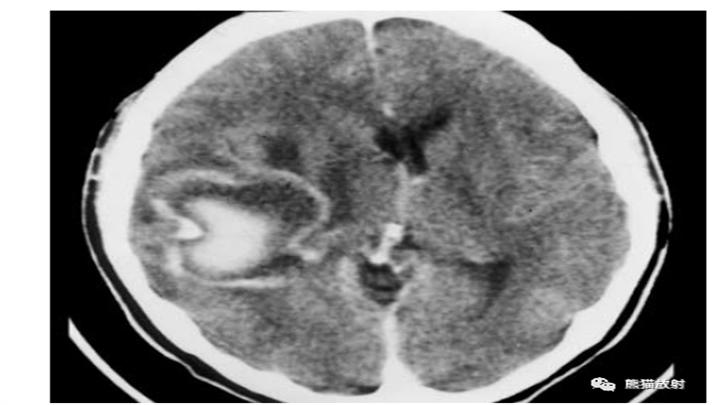

液平面的存在并不罕见(血液在倾斜面处分层)。上图示大的壳核血肿,表现为深部的较新的致密的成分,而其外侧浅表的血肿,以清晰的液-液平面为特征(箭)。下图示一接受抗凝治疗的心脏病发作患者,不规则且广泛分布的多灶性实质内出血中,也可以观察到液-液平面(箭)。